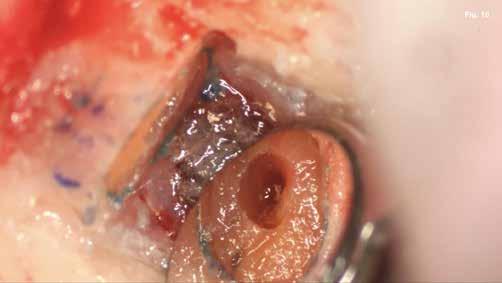

A szubmarginális teljes vastagságú lebenyt két felszabadító bemetszéssel végeztük egy 69-es számú, dupla lekerekített mikropengével (Swann–Morton) (6–7. ábra) A vestibularis csont ép volt, ezért csontablak-technikát alkalmaztunk és végeztünk (6–8. ábra) piezo készülékkel (Woodpecker DTE AI Surgery) és „US1, UC1” (Guilin Woodpecker Medical Instrument Co., LTD) hegyekkel. A blokkot az intraoperatív szakaszok alatt sóoldatban tartot-

tuk. Az apikális reszekciót (8. ábra) az „UC1” (Guilin Woodpecker Medical Instrument Co., LTD) segítségével végeztük el, és a gyökeret egy 3 mm-es „MM4” (Hu-Friedy Manufacturing Co. LLC) kerek tükörrel vizsgáltuk a VRF szempontjából (13. ábra). A gyökérvég polírozását (11. ábra) az „UL4” (Guilin Woodpecker Medical Instrument Co., LTD) segítségével végeztük. A csontos kripta küretizálása kézi küretezéssel történt, de a csontos kriptában lévő további hámbélés eltávolításával a gyógyulási folyamat felgyorsítása érdekében piezo „UL3” (Guilin Woodpecker Medical Instrument Co., LTD) piezo hegyet is használtunk (9–10. ábra). A három mm-es retropreparációt (14–17. ábra) a „JT2SA” hegy (B&L Biotech) segítségével végeztük el. A retropreparációt ismét ellenőriztük a guttapercha maradványok tekintetében, leöblítettük és papírhegyekkel meg-

szárítottuk (18–20. ábra), majd retropecsétet (21–23. ábra) készítettünk „Neo Mta plus” (Avalon Biomed). A csontos blokkot visszahelyeztük (24. ábra) az eredeti helyzetébe, és a „Jason membrán” (Botiss Biomaterials GmbH) reszorbálható kollagénmembránt használtunk a blokkablak lefedésére (25. ábra). A lágyrészek varrására (26. ábra) nem felszívódó 6,0 monofilamentumos varratokat használtunk (SMI), amelyeket az 5. napon eltávolítottunk (27. ábra).